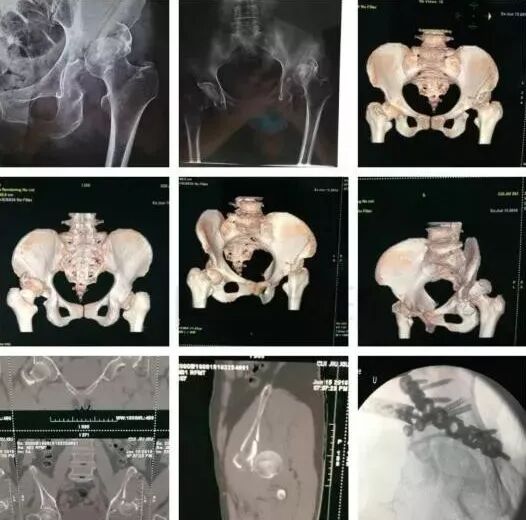

2)骨盆骨折

30min,三个决定:

• 开放性骨折,立即止血;

• 骨盆制动(10-15min);

• 观察10-15min,血流动力不稳定,能否手术?

图片

血流动力学稳定,在7天内手术?

3)髋臼骨折(伤后5-7天)

• 人体最大的负重关节,精确复位可达到关节的最佳匹配,确保正常力学性能;

• 影像学移位程度大,不匹配>2mm--手术;

• 髋关节脱位,髋臼后壁骨折并股骨头骨折,复位后关节仍然不稳,或关节腔有游离骨块--手术。

并发症:异位骨化18-90%;股骨头坏死3-9%